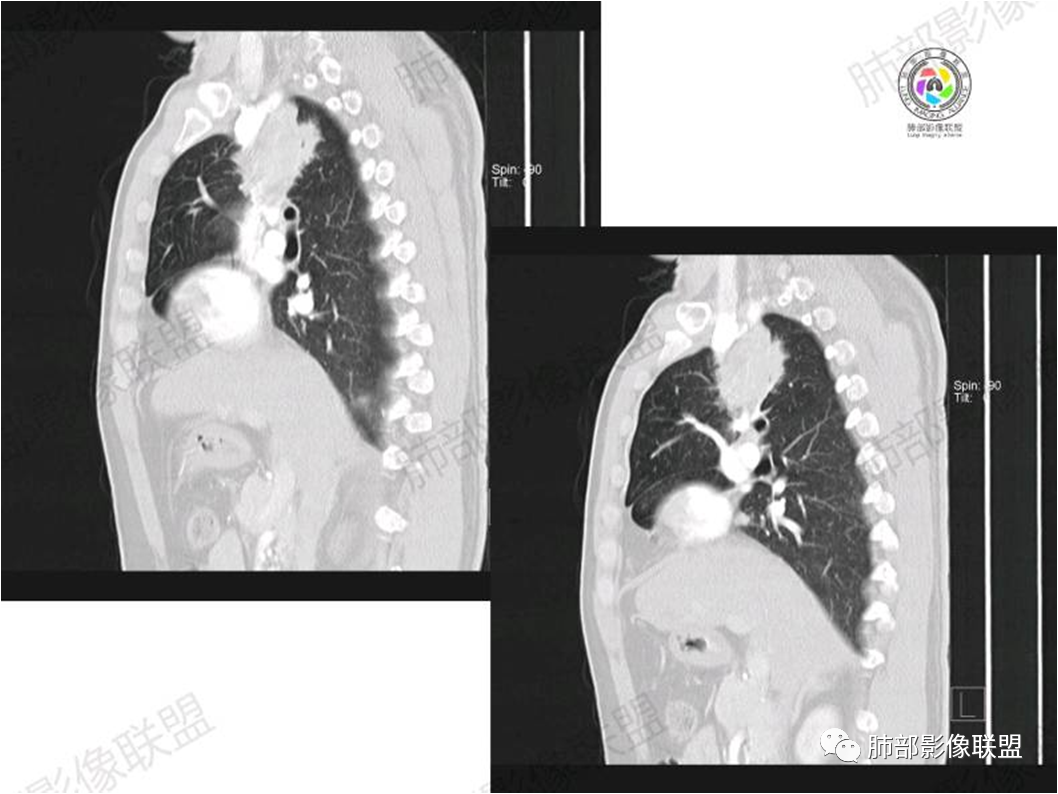

病灶紧贴纵隔胸膜

糊墙,胸膜外未见明显侵犯迹象

病灶整体狭长一些

边缘平直、凹陷为主

支气管外侧带的通畅,片内侧带的似乎中近端狭窄,堵塞

内部肺动脉走形还可以

近端支气管壁弥漫增厚

强化均匀

整体炎性的特点比较明显

不踏实的地方:

边上有些毛糙

恶性待排除

恶性:还是淋巴瘤多见一些。